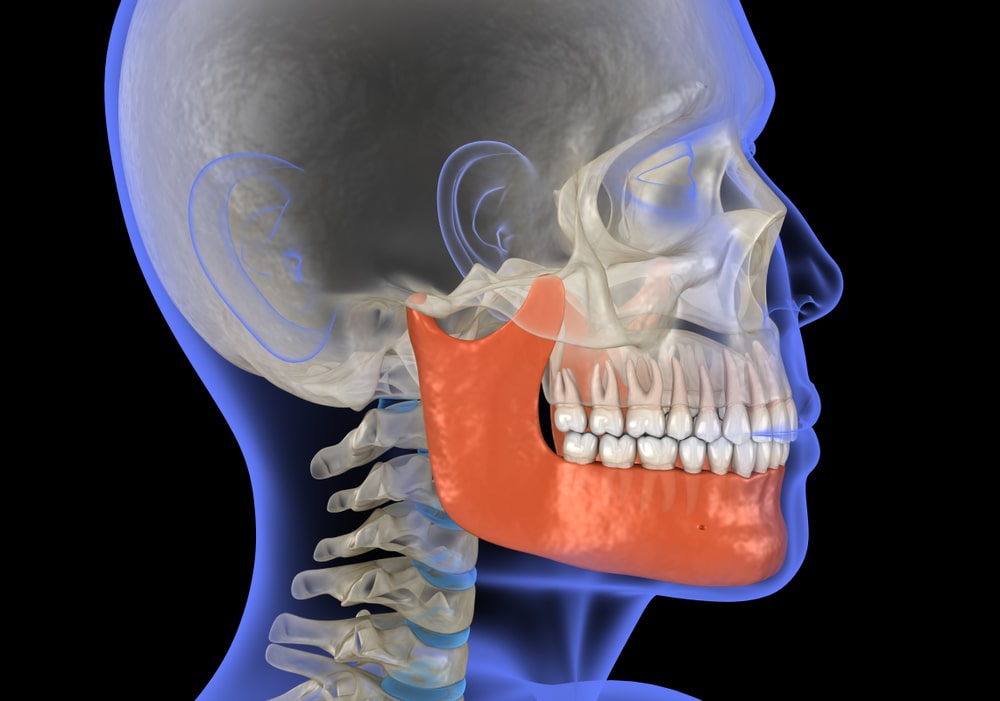

Did you know that mouth breathing, lip seal, and improper tongue posture can cause disharmonies in the jaw and lead to irregular jaw growth? One way that orthodontists are treating jaw problems is through facial growth orthodontics, a method of correcting and remodelling the mid-face and upper jaw by stimulating the nerves in the palate.

Traditional orthodontics (typically, braces or surgery) straightens teeth to create a nice smile. However, traditional methods don’t address jaw position and face development. Sometimes, when patients with an underdeveloped jaw don’t have enough “room” for teeth because of an underdeveloped jaw, the recommended course of action is to remove some teeth. However, this can make the jaw smaller and lead to loss of structure and facial aesthetics.

With facial growth orthodontics or controlled arch orthodontics, the goal is to adapt tooth movement to the patient’s natural facial characteristics. Instead of seeking to simply straighten the teeth, the goal of this method is to help the jaw reach its proper size for correct function and improved physiological appearance.

The treatment uses a fixed growth guided appliance (FGGA) and removable growth guided appliance (RGGA), which puts light pressure on the nasopalatine nerve to stimulate development. Over time, the result is a remodel of the patient’s mid-face.